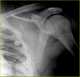

Osteopoikilosis

Osteopoikilosis is a benign, autosomal dominant sclerosing dysplasia of bone characterized by the presence of numerous bone islands in the skeleton. Presentation The radiographic appearance of osteopoikilosis on an X-ray is characterized by a pattern of numerous white densities of similar size spread throughout all the bones. [Source: Wikipedia ]